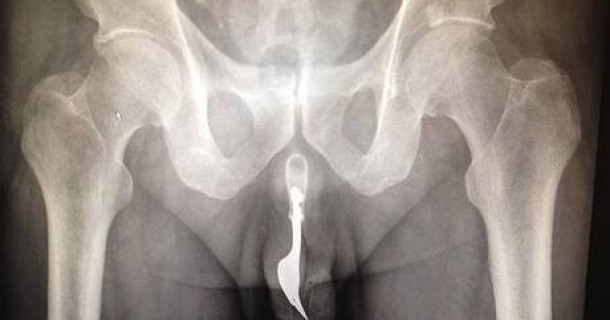

Անանուն 70 ամյա սուր զգացողությունների սիրահարը տեղափոխվել է Քանբերիի հիվանդանոց արյունոտ առնանդամով: Ընդ որում պատառաքաղը առնանդամի ներսում չի երևացել , այլ բժիշկները այն զգացել են միայն շոշափելով և երևացել է ռենտգենյան նկարներում:

Պատառաքաղը հաջողվել է սեռական օրգանից դուրս բերել միայն ընդհանուր անզգայացման միջոցով: Վիրահատությունը անցել է հաջող: Տարեց հիվանդին ուղարկել են տուն: